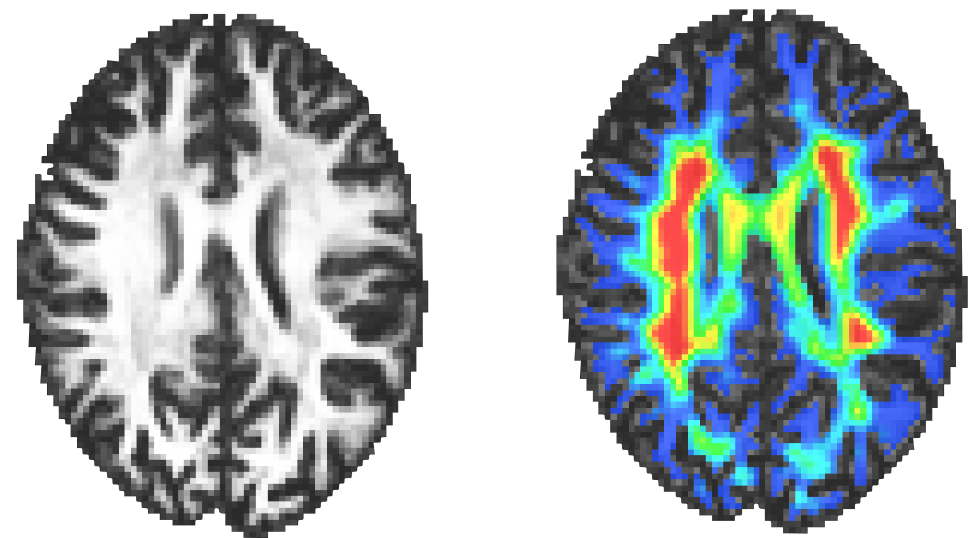

This repository contains a package facilitating the tracking of sub-cortical U-Fibers. The main function of this package is the creation of angular maps, enabling a tractography with a position-dependent maximum angle between tractography steps. The function creating these angular maps is wmfod_to_angle in the core.py file.